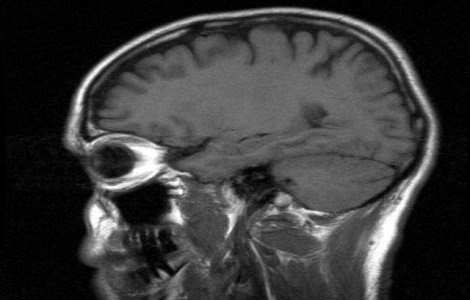

Pilotii care zboara adeseori la altitudini mari prezinta un risc crescut de leziuni cerebrale, afirma autorii unui studiu publicat luni in revista americana Neurology.